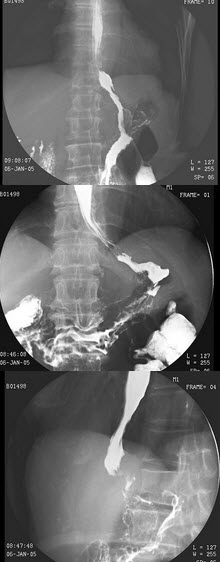

16、单项选择题

男,9岁,脸色苍白5月。上腹部不规则疼痛。大便潜血(+),血红蛋白61g/L,结合图像,最可能的诊断为()

A.正常表现

B.胃窦炎

C.球部溃疡

D.十二指肠球炎

E.球后溃疡

31、单项选择题

男,56岁,胸骨后不适3月,吞咽时异物感,如图,最可能的诊断是()

女,50岁,胃体贲门癌术后3月余,自诉进食有梗阻感,结合图像,最可能的诊断为()

A.吻合口通畅

C.肺奴卡菌病

D.肺放线菌病